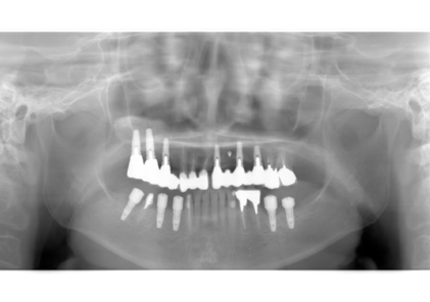

24.パノラマレントゲン

↑2006年4月24日(初診時)

↑2024年6月26日

25.初診より18年経過(2024年6月26日)